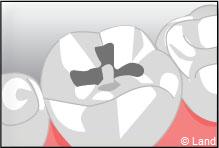

Un inlay reconstitue l’anatomie dentaire en comblant une cavité taillée dans la dent.

L’onlay intéresse aussi la surface occlusale (masticatoire) de la dent.